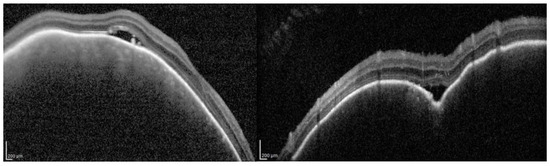

- Cacciamani, A.; Scarinci, F.; Parravano, M.; Giorno, P.; Varano, M. Choroidal thickness changes with photodynamic therapy for a diffuse choroidal hemangioma in Sturge–Weber syndrome. Int. Ophthalmol. 2014, 34, 1131–1135. [Google Scholar] [CrossRef] [PubMed]

- Spaide, R.F.; Koizumi, H.; Pozzoni, M.C. Enhanced depth imaging spectral-domain optical coherence tomography. Am. J. Ophthalmol. 2008, 146, 496–500. [Google Scholar] [CrossRef] [PubMed]

- Margolis, R.; Spaide, R.F. A pilot study of enhanced depth imaging optical coherence tomography of the choroid in normal eyes. Am. J. Ophthalmol. 2009, 147, 811–815. [Google Scholar] [CrossRef] [PubMed]

- Arora, K.S.; Quigley, H.A.; Comi, A.M.; Miller, R.B.; Jampel, H.D. Increased choroidal thickness in patients with Sturge-Weber syndrome. JAMA Ophthalmol. 2013, 131, 1216–1219. [Google Scholar] [CrossRef] [PubMed]

- Ciancimino, C.; Di Pippo, M.; Rullo, D.; Ruggeri, F.; Grassi, F.; Scuderi, G.; Abdolrahimzadeh, S. An Update on Multimodal Ophthalmological Imaging of Diffuse Choroidal Hemangioma in Sturge-Weber Syndrome. Vision 2023, 7, 64. [Google Scholar] [CrossRef] [PubMed] [PubMed Central]